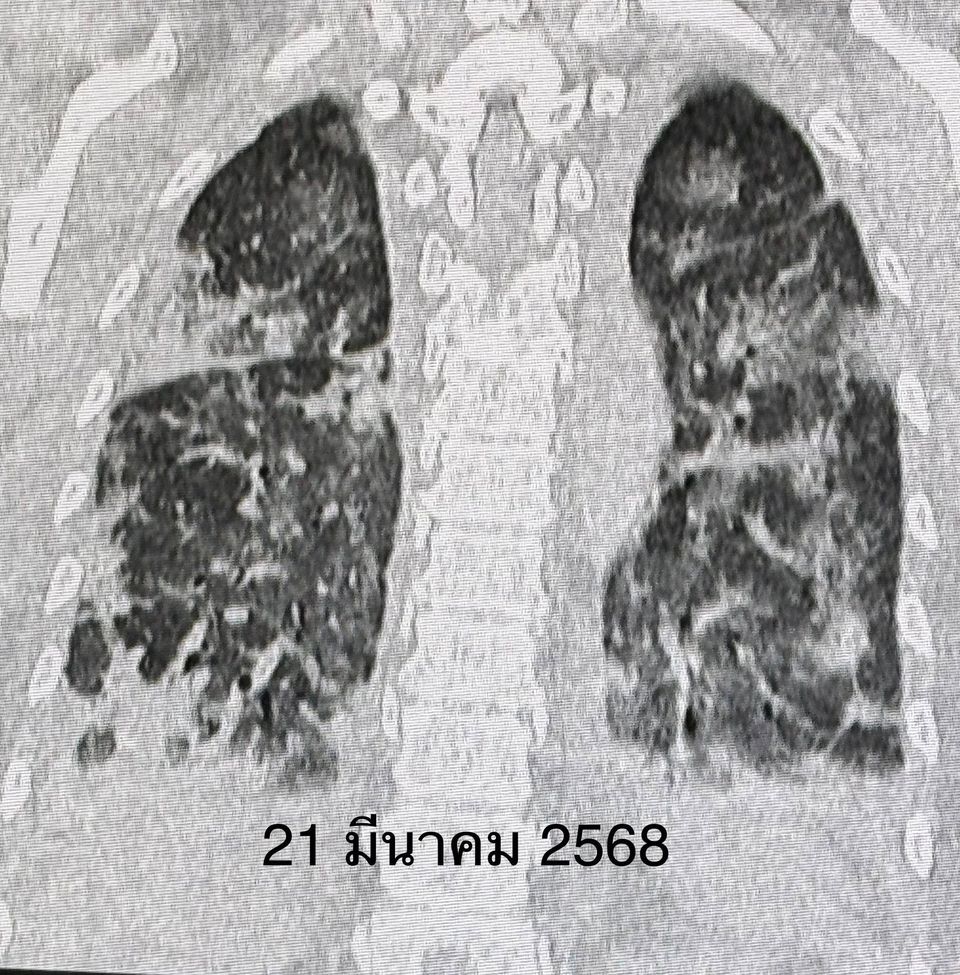

เจาะเลือด พบเลือดจางเล็กน้อย ค่าอักเสบในเลือด ESR และ hs-CRP สูง, ANA ปกติ ค่าโซเดียมในเลือดต่ำ เอกซเรย์ปอดและคอมพิวเตอร์ปอดพบปอดอักเสบทั้ง 2 ข้าง แยงจมูก ส่งเลือดเพาะเชื้อ ส่องกล้องเข้าไปในหลอดลม ไม่พบการติดเชื้อแบคทีเรีย ไวรัส เชื้อรา หรือวัณโรค ได้ยาปฏิชีวนะ เอกซเรย์ปอดซ้ำไม่ดีขึ้น หลังรักษาที่โรงพยาบาลใกล้บ้าน 26 วัน ญาติขอย้ายมารักษาต่อวันที่ 11 เม.ย.68

วันที่ย้ายมา หลังจากซักประวัติ ตรวจร่างกาย และทบทวนประวัติเดิม คิดถึงโรคภูมิต้านทานตนเอง (Autoimmune Diseases) ทำให้เกิดโรคเนื้อเยื่อปอดอักเสบ หรือ Interstitial lung disease (ILD) มากที่สุด ส่งเลือดตรวจพบ Anti MDA5 และ Anti-Ro52 บวก ค่า Ferritin สูง ค่า CPK ของกล้ามเนื้อปกติ ค่าเอนไซม์ของตับสูงเล็กน้อย ค่าไตปกติ ระดับโซเดียมในเลือดต่ำเกิดจาก Syndrome of inappropriate ADH (SIADH)

วินิจฉัยว่า ผู้ป่วยรายนี้เป็นโรคภูมิต้านทานตัวเองชนิด Anti-MDA5 antibody positive dermatomyositis ทำให้เนื้อเยื่อปอดอักเสบ และปอดเกิดพังผืดอย่างรวดเร็ว ไม่มีกล้ามเนื้ออ่อนแรง ไม่มีความผิดปกติของผิวหนังให้ยาสเตียรอยด์ชนิดฉีดขนาดสูง ต่อมาเปลี่ยนเป็นชนิดกิน ยากดภูมิคุ้มกันไมโคฟีโนเลต (mycophenolate) ยาไฮดรอกซีคลอโรควิน (hydroxychloroquine) และยา Tolvaptan รักษาโรคโซเดียมในเลือดต่ำ